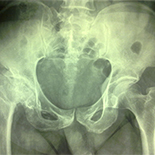

We deeloped a novel technique – fast mobile-window small incision (FMWSI) – a modification of minimally invasive surgery for total hip arthroplasty, which we believe is particularly suited to elderly patients with hip fractures. The present article aimed to introduce this technique and compare the clinical effects between the FMWSI technique and conventional incision (CI) for hip arthroplasty in elderly patients.

This study included 240 consecutive patients who underwent hip arthroplasty. Half received total hip arthroplasty and half received hemi hip arthroplasty. The 120 patients in each group were further divided into FMWSI and CI groups. The following parameters were compared between the FMWSI and CI groups: length of incision, operation time, bleeding volume, drainage volume, postoperative ambulation time, and Harris score.